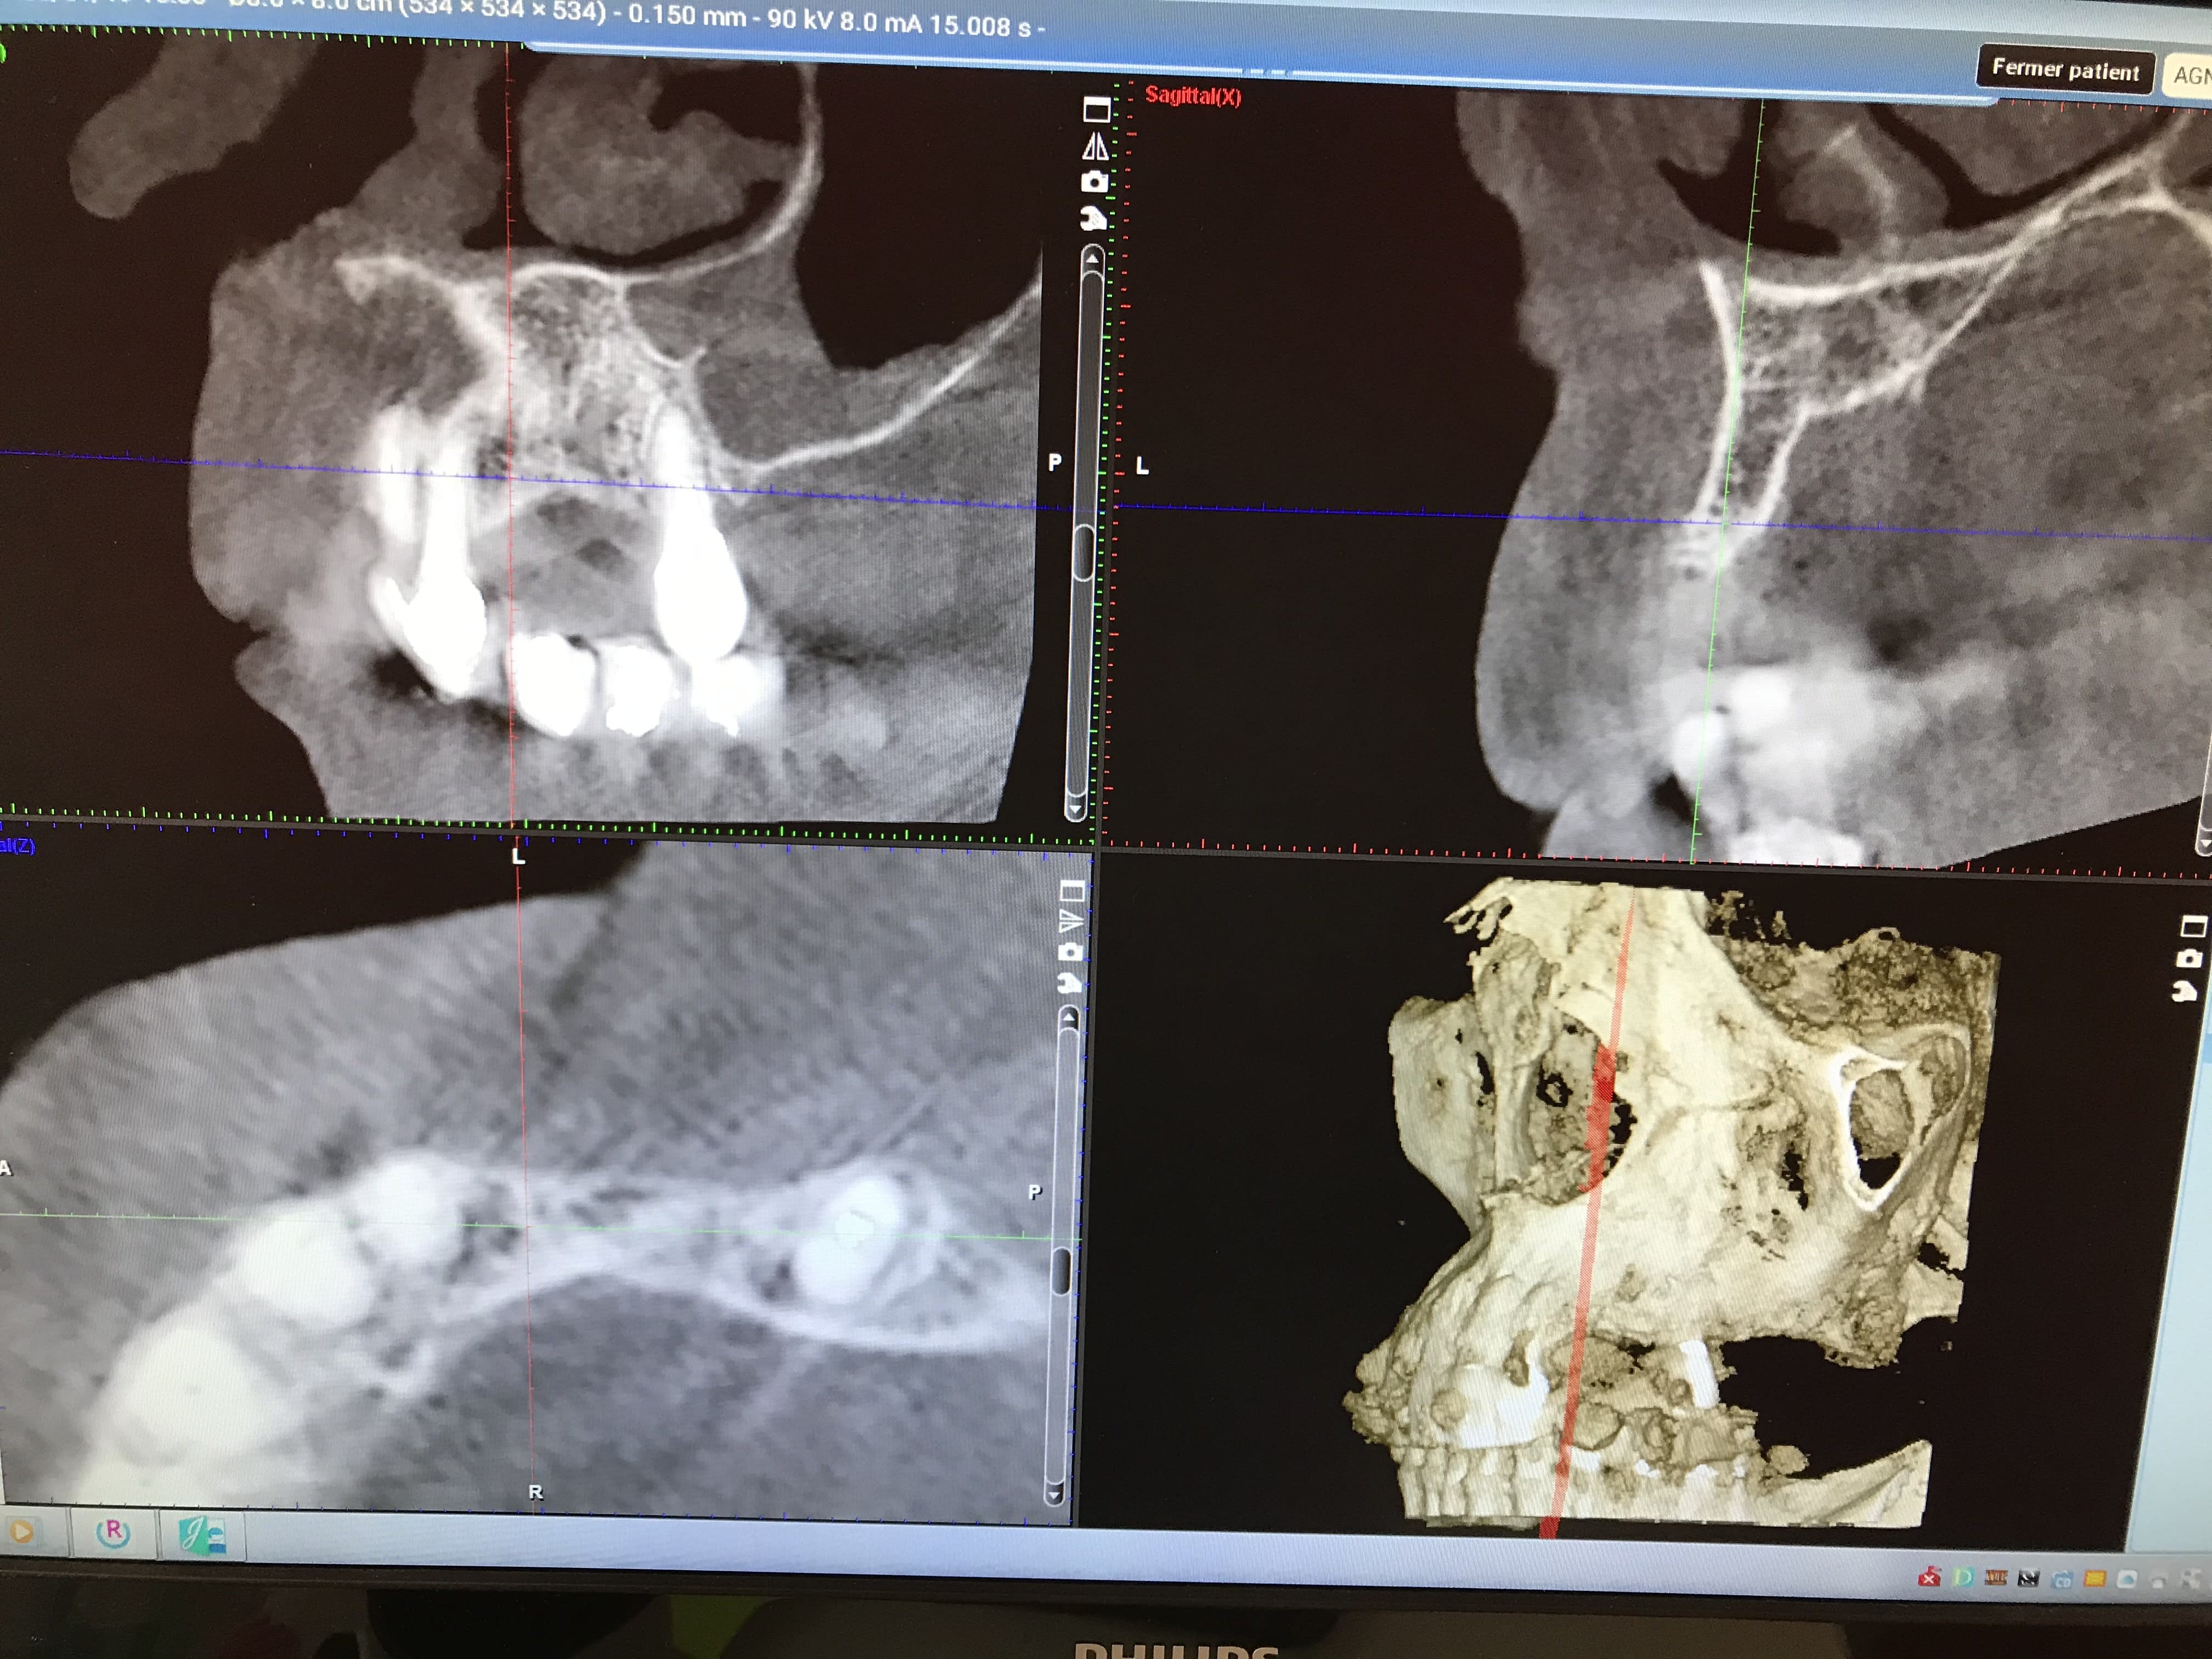

Patiente avec pilier de bridge 13 fracturé + 15 paro mobile + 25 paro mobile + 22 légèrement mobile. Les seules dents "viables" sur l'arcade sont 11, 21 et 22 et la 12 a été extraite entre temps.

Sur les coupes conebeam, très peu d'os au niveau de 13 et surtout 14 en épaisseur, un peu plus au niveau de 23 et 24 et pas assez d'os au niveau de 15 et 25 (présence des sinus).